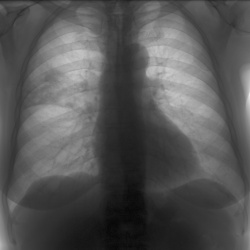

Здравствуйте, мужчина 69 лет, неделю назад выставлена пневмони, жалобы на кашель и температуру. Можно сказать что динамика положительная? Вижу слабо-положительную динамику. Или её нет и лучше...